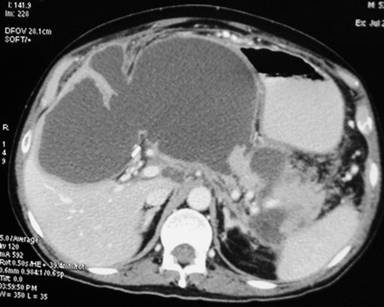

A 53-year-old man had undergone a laparoscopic cholecystectomy at another hospital for biliary acute pancreatitis on the fourth day of the onset of abdominal pain. The risk stratification of acute pancreatitis prior to laparoscopic cholecystectomy is not available. Postoperatively, he developed exacerbation of the pancreatitis with fever, abdominal pain and leukocytosis. He improved with conservative management and was discharged. He was readmitted to the same hospital with increased abdominal pain and fever. A CECT abdomen carried out approximately 2 weeks after the surgery revealed multiple fluid collections in the entire pancreas, lesser sac, hepatogastric ligament, pancreatic tail and along the left paracolic gutter (Figure 1).

Figure 1. CECT abdomen showing a large intrapancreatic fluid collection extending into the hepatogastric ligament. Two additional fluid collections around the tail of the pancreas are seen. A viable pancreatic parenchyma upstream in the tail region is evident. |